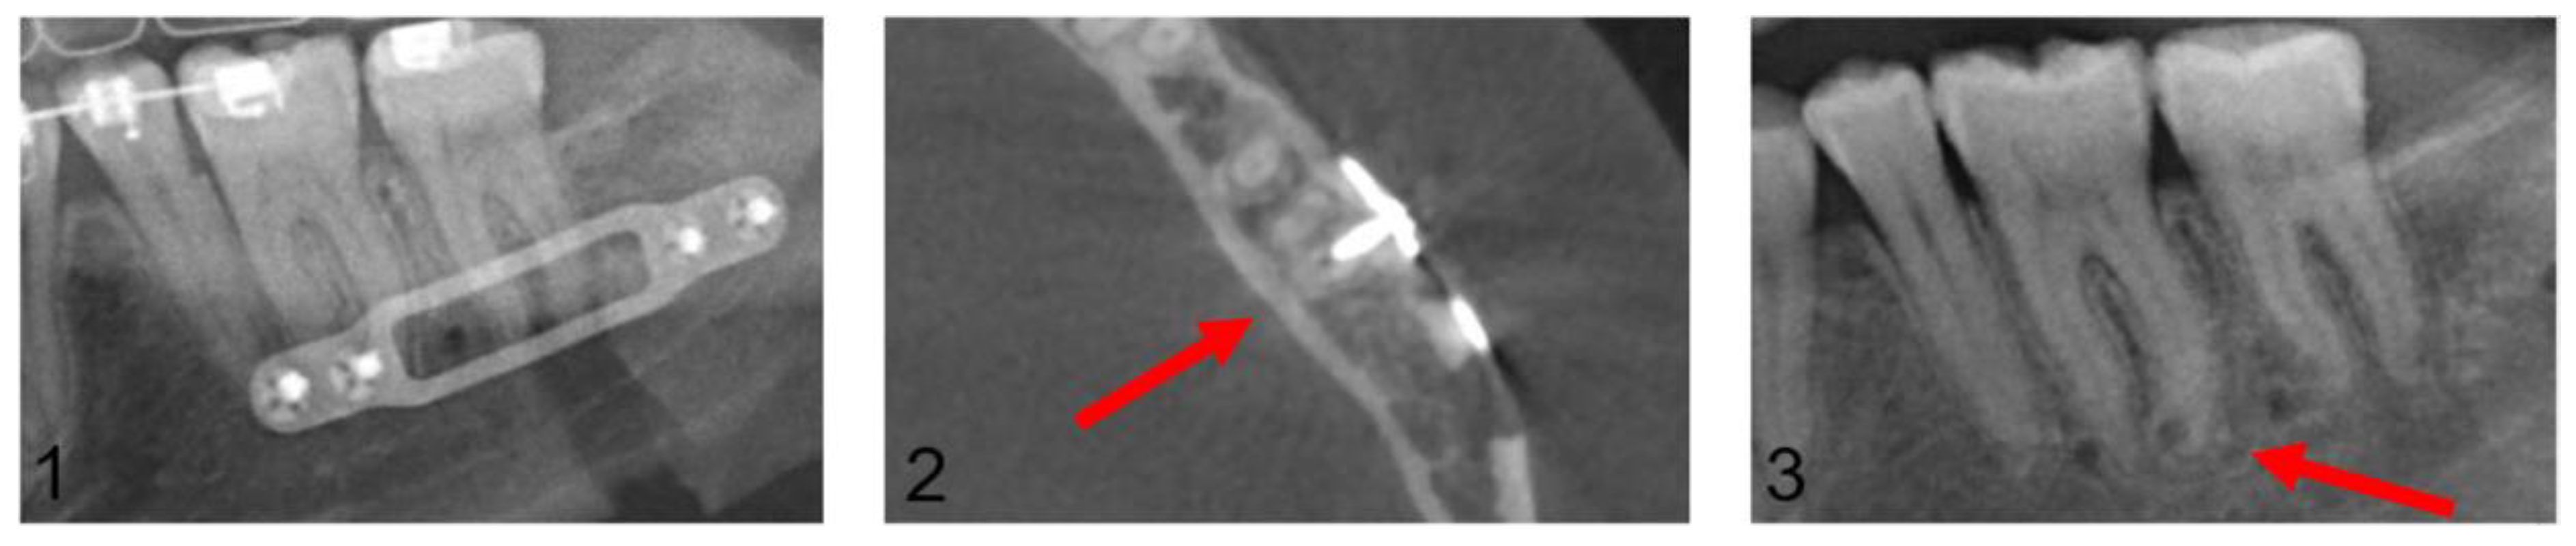

Figure 6 and Figure 7 present a patient case after conventional maxillary positioning, showing projections of osteosynthesis screws with the dental roots in the OPG and, subsequently, the confirmed or not confirmed dental injuries in the CT scan.

Figure 6.

Post-operative orthopantomogram after the conventional maxillary positioning, showing the projections of three osteosynthesis screws with the dental roots of the teeth 16 and 17 and the projections of four osteosynthesis screws with the dental roots of the teeth 26 and 27 (red arrows).

Figure 7.

Axial plane of post-operative CT scan. Image (1) shows an injury of the mesiobuccal tooth root of tooth 27, while in image (2), no root injury in the right maxillary molars is detected (red arrows).

In the Maxilla Conventional cohort, 94 radiological projections of osteosynthesis screws with the dental roots were detected in the post-operative OPG. In contrast, post-operative CT imaging detected only 10 dental root injuries. In the Maxilla PSI cohort, 64 radiological projections were detected; however, no dental root injury could be detected in post-operative CT imaging. In the mandible, a total of 106 projections in the premolar and molar region were recorded in the post-operative OPG, but only 12 root lesions were detected in post-operative CT scan.